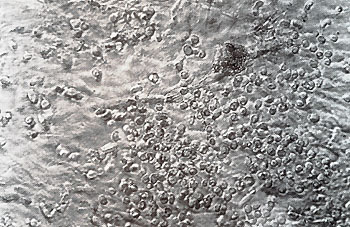

Table 1 demonstrates that adipocyte-containing confluent stromal layers could be initiated and maintained for periods of at least 5 months in either Fischer's or McCoy's medium when supplemented with both horse serum and hydrocortisone. The stromal layers of very old cultures (greater than 6 months ), especially those grown in Fischer's medium, were comprised almost exclusively of adipocytes (Fig. 1 ). Greenberger ( 1979) also reported the induction by corticosteroids of lipogenesis in adipocytes in human marrow cultures. In the absence of horse serum, either medium, despite supplementation with hydrocortisone and FBS, failed to support the development of significant numbers of lipid-Iaden adipocytes. In such cultures almost no nonadherent cells were recovered after 6-8 weeks. Cultures grown in McCoy's medium supplemented with FBS with or without HoS developed confluent

Fig. I. A human marrow culture at 6 months illustrating abundant adipocytes. X 20

stromal layers earlier than those supplemented with HoS alone or grown in Fischer's medium. Fischer's growth medium supplemented with hydrocortisone and 25% HoS or 12.5% HoS and 12.5% FBS was able to support the generation of CFUc-forming cells for up to 12 weeks in some cases. However, the number of colony-forming cells recovered from such cultures was usually less than 50 per 105 cells assayed. In contrast, McCoy's complete growth medium supplemented with both FBS and HoS not only provided adequate nutrition for the early development and maintenance of stromal layers containing abundant adipocytes but also contributed either directly or indirectly (through the stromal microenvironment) to longterm hematopoiesis and significantly greater yields of CFU c. Figure 2 illustrates the appearance of a typical culture at day 14. A confluent stromal layer can be seen underneath the nonadherent cells. A most important feature of these long- term cultures is the presence of "cobblestone"-like areas, presumably regions of hematopoiesis from which the nonadherent cells arise. Figures 3 and 4 illustrate such cobblestone-like areas in cultures at 6 weeks and 16 weeks, respectively. At higher magnification (Fig. 5), the flattened polygonal cells in such areas are seen to be so tightly packed together that their boundaries may be difficult to discern. With time some of these cells become more rounded granules can be seen to appear within their cytoplasms and ultimately they become nonadherent. When coverslip cultures were gently washed extensively to remove non adherent cells and stained for myeloperoxidase activity, it was observed that cobblestone areas did indeed contain both myeloid and monocytoid cells. Coverslip cultures stained for nonspecific esterase activity revealed monocytoid cells scattered throughout the stromal layer , in islands of hematopoiesis, and sometimes in large, tight clusters within the stromal layer. In general, nonspecific esterase-positive cells were much more intensively stained outside of the cobblestone areas. The kinetics of the generation of cells with colony-forming ability in these long-term cultures appeared to follow two different patterns, designated the "hyperproliferative" and "homeostatic" patterns. The hyperproliferative pattern describes cultures in which the